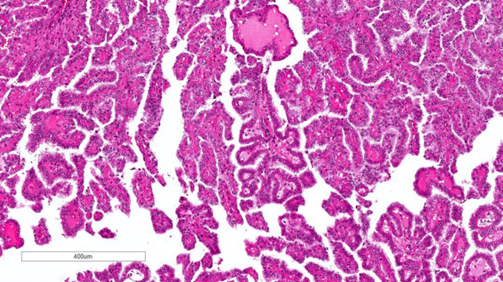

Kiến trúc chủ yếu là dạng nhú hoặc dạng ống–nhú. Lớp lót gồm các tế bào có hình thái đa dạng, từ các tế bào vuông nhỏ bắt màu kiềm với hạch nhân không rõ cho đến các tế bào lớn hơn, bào tương eosin với hạch nhân nổi bật; có thể gặp bào tương sáng, đây là một bẫy chẩn đoán đã biết trong ung thư biểu mô tế bào thận dạng nhú. Các tế bào có thể sắp xếp theo kiểu hàng thẳng hoặc giả tầng. Tính không đồng nhất và hình thái hỗn hợp rất thường gặp, chiếm khoảng 47–48% các trường hợp, do đó đây là một trong những lý do khiến việc phân typ không còn được ưu tiên. Thường thấy thâm nhiễm các đại thực bào bọt. Có thể hiện diện các thể cát vôi (psammoma bodies) và sắc tố hemosiderin. Các kiểu hình đã được mô tả gồm: dạng PRCC hai pha (biphasic, phế nang hoặc squamoid), với hai quần thể tế bào, các ổ tế bào lớn hơn dạng squamoid, bào tương eosin, được bao quanh bởi các tế bào nhỏ hơn bắt màu amphophilic tạo thành cấu trúc phế nang; đã ghi nhận bằng chứng diễn tiến ác tính ở tối đa khoảng 15% trường hợp. Dạng PRCC kiểu Warthin, với các nhú bào tương eosin kèm thâm nhiễm lympho dày đặc, tương tự u Warthin của tuyến nước bọt; thường là các khối u độ mô học cao và có thể biểu hiện diễn tiến lâm sàng ác tính. Dạng PRCC đặc hoặc giả đặc, với kiến trúc đặc do các cấu trúc ống và nhú bị nén ép, được lót bởi các tế bào nhỏ có nhân độ thấp; được ghi nhận có diễn tiến lâm sàng tương đối lành tính. Các kiểu kiến trúc mô học liên quan đến tiên lượng xấu hơn bao gồm dạng đặc, dạng vi nhú, hiện tượng hobnailing và kiến trúc vi nang. Hệ thống phân độ WHO/ISUP đã được xác nhận là một yếu tố tiên lượng đối với PRCC, dựa trên mức độ nổi bật của hạch nhân để phân độ 1 đến 3, và dựa trên đa hình nhân tế bào hoặc biệt hóa dạng sarcomatoid hay rhabdoid cho độ 4.

Hình 8. pRCC đặc trưng bởi cấu trúc chủ yếu dạng nhú hoặc ống‑nhú